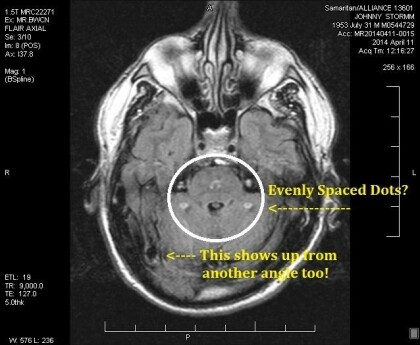

By the Spring of 2014, I got my MRIs back from Samaritan Hospital in Watertown, New York after MUCH malarkey from my doctors and the hospital refusing to let the judge see them and denying they happened. But my insurance paid for it all and I was entitled⦠and talented enough to dominate the nurses and receptionist to give me the actual disk my MRIs were recorded upon. I used them to win my case with Social Security. However, when I poured over the pictures, I was SHOCKED beyond words to see whole patterns of foreign implants within the deep places in my brain! To make matters even WORSE, another ULTRA from the UK was currently showing his MRIs and telling people how he was being controlled by these! I was having black outs and going through all sorts of things that left me in terror of what I might be doing out on the streets without having any clue that I was up and doing anything at all! Would I be going to prison for some strange murder they put me up to? I really had no clue and that worried me GREATLY! I never wanted to be one of those disposable, one-time use ULTRAs, and it looked like I had no way to stop it from happening anyway. I was VERY afraid!